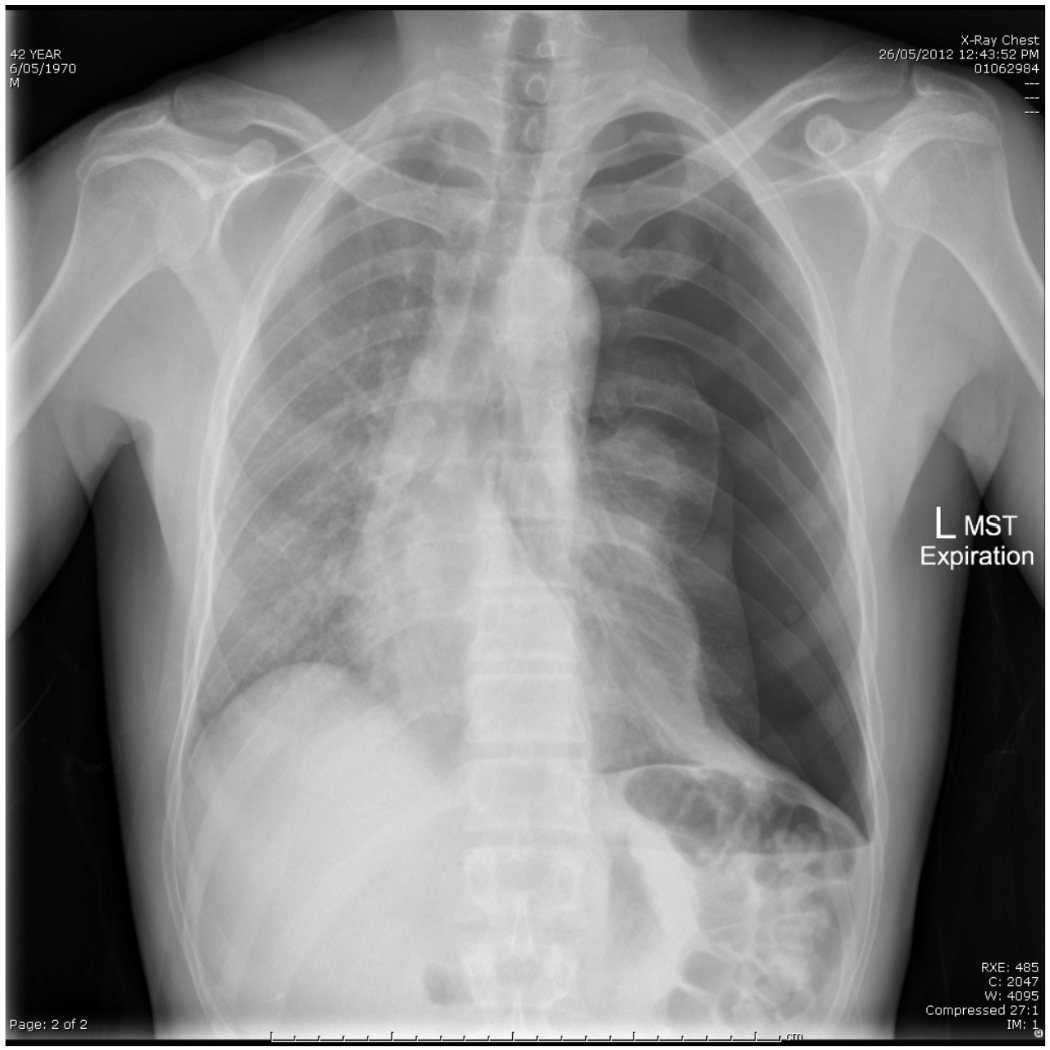

An 18 year old male presents with chest pain. A CXR is taken- refer to the props booklet- page 4.

a. State two (2) abnormal findings shown in this xray. (2 marks)

b. State four (4) likely precipitating causes. For each cause, state the definitive management of the condition. (8 marks)

Soon after this xray is taken, the patient becomes distressed and is noted to have a BP of 75/40 with HR 170 /min.

c. State two (2) immediate steps in the treatment of this patient. (2 marks)